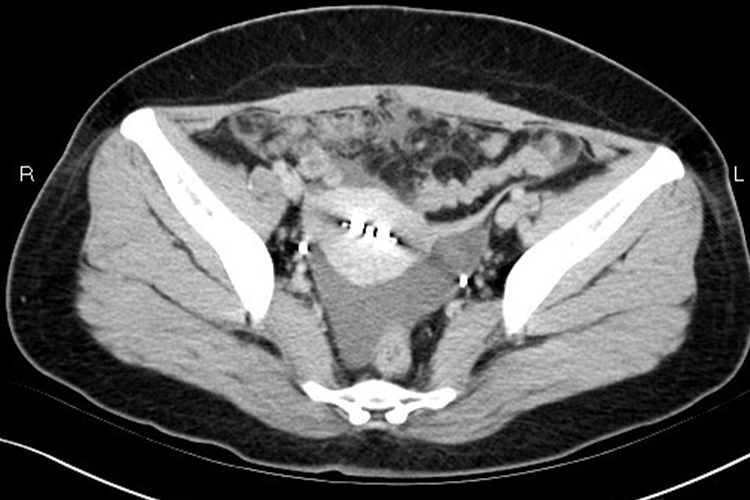

1、生理性盆腔积液:根据患者临床表现,影像学检查CT、MRI表现为水样密度/信号量较少,排卵后液体较多,盆腔各器官均无异常改变,可明确诊断。

2、病理性盆腔积液:根据患者临床表现,出现下腹痛、腰骶痛,腰酸等。影像学检查病理性盆腔积液量较生理性盆腔积液多,少量时多位于病变周围或包裹于某部位,液体因含成分不同,CT密度或MRI信号可有不同,同时可见腹膜和盆腔脏器病变,可明确诊断。